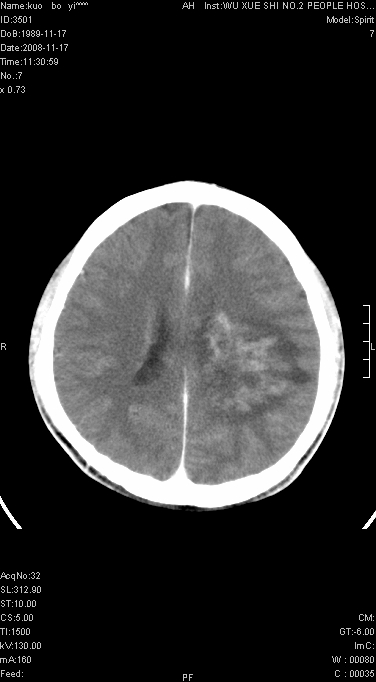

增强后水肿中心高密度灶有明显强化,强化不均匀,呈雪花状或絮状,且强化明显,若为肿瘤,应该出现形态较规则的瘤体影,强也有例外如胶质瘤就可以形态不规则.但胶质瘤明显强化者多为恶性间变性,与病史及相关表现太不相符.因此本例多考虑为炎症引起.

本例与重庆中华放射学年会读片大赛上第12个病例(由山东医影研究所柳澄教授提供)有异曲同工之妙(影像表现几乎相同).那个病例我的第一选择是炎症,其次是血管畸形,最后选项择的占位.但得到的答案是ms,新发的ms灶可见明显强化,但这么大的病灶着实没有想到,可能本例就影像表现来说也不能排除ms可能

还是考虑原发脑胶质瘤,梗塞缺血水肿的低密度要同时累及皮、髓质并要符合动脉供血的区域分界特点,本例强化后见瘤体结节及向周围浸润生长的瘤血管都强化了,水肿广泛呈指状,占位效应使同侧脑皮质受压变薄、脑沟消失但因实质性的瘤体尚小所以中线无明显移位。不知各位同意这样分析吗?(转移瘤多为多处病灶)

首先考虑脑胶质瘤。有明显的左顶叶脑白质水肿,病变轻度占位效应,花环样强化,脑炎——影像不支持!